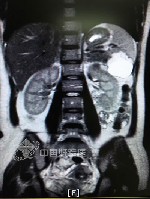

本報訊(通訊員 何雷 王吟雪)7月15日16點(diǎn)30分左右,在第三軍醫(yī)大學(xué)西南醫(yī)院正在進(jìn)行一次緊急手術(shù),肝膽科和婦產(chǎn)科正緊密合作,為一位十分罕見的宮外孕患者進(jìn)行部分脾臟切除手術(shù)。在切除的一半脾臟里,一個嬰兒已發(fā)育約有3個月大小,肉眼可見清晰的頭、臉、鼻子、眼睛、四肢等。

王婷同意了該B超醫(yī)師的意見,增加了肝膽胰脾腎超聲檢查項目。隨后,脾臟部位,一個活生生的胎兒被發(fā)現(xiàn)。